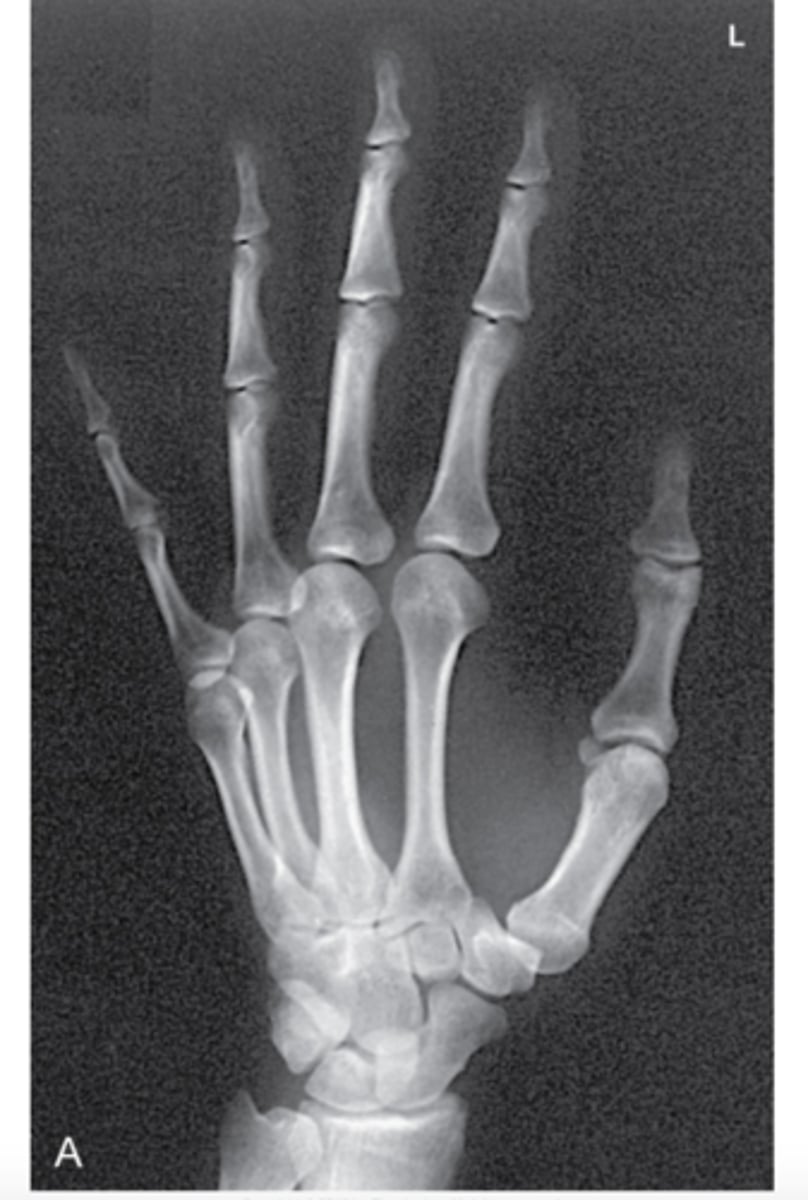

In an x-ray of a hand, the bones _________ more radiation than the surrounding tissue, therefore, they cast heavier "shadows' on the scan.

Attenuate

What color are "shadows" on x-ray film?

White

Where x-rays have reached the film, the film is exposed & turns ___________.

Black